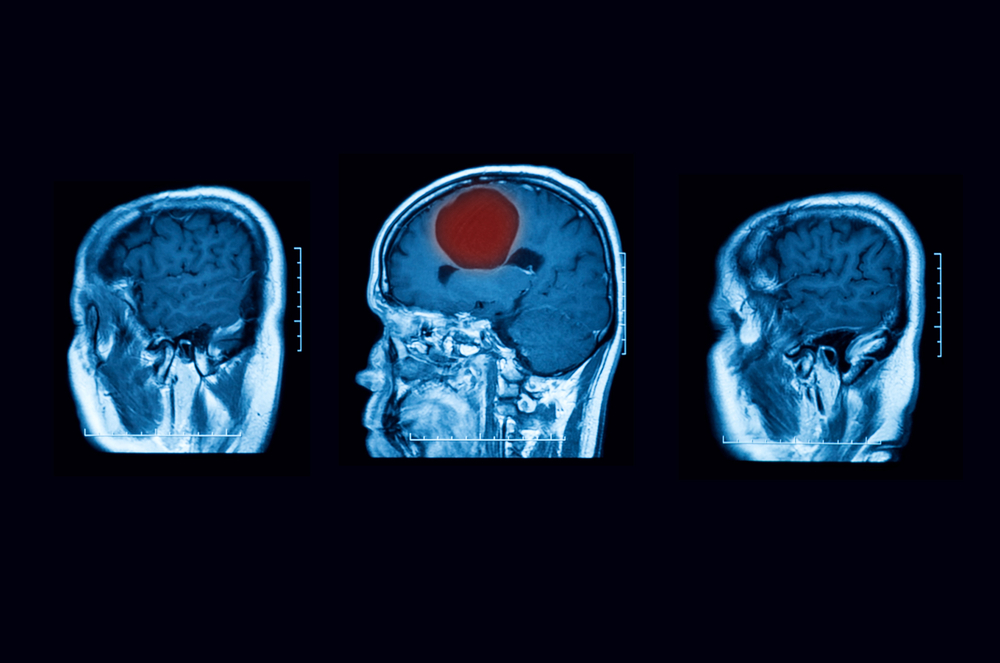

Принципы диагностики

Из дополнительных диагностических методов для подтверждения диагноза особое значение имеет:

- компьютерная томография (наиболее информативна при инкапсулированных абсцессах; на ранних стадиях болезни ценность метода снижается);

- МРТ (позволяет точно поставить диагноз).